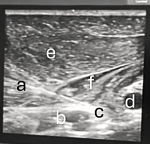

Following sonographic identification of the anatomical structures within the infraclavicular fossa, including subcutaneous tissues, the pectoralis major and minor muscles, and the neurovascular bundles, an insulated 21-gauge, 100 mm Stimuplex®A needle was advanced using an in-plane approach under ultrasound guidance at angles up to 45° (Figure 1) and through the pectoralis muscles, targeting the space between the axillary vein and artery (Figure 2). Real-time visualisation of the needle shaft and tip was maintained, with initial advancement directed toward the medial cord of the brachial plexus. A 10 mL syringe containing 0.25% bupivacaine with adrenaline was attached and flushed. The first 5 mL of local anaesthetic was administered without resistance near the medial cord (Figure 2), and its spread was observed surrounding the medial cord and displacing cephalad the axillary. The injection effectively increased the distance between the artery and vein, facilitating needle repositioning and pass towards the posterior cord, where 10 mL of local anaesthetic was administered (Figure 3). Subsequently, the needle was redirected to reach and target the lateral cord (Figure 4), and the remaining 5 mL of local anaesthetic was deposited at this location, with satisfactory circumferential spread observed around the axillary artery. Throughout all needle insertions and repositioning, the assistant performed aspirations before each injection to minimise the risk of intraneural injection, vascular puncture, and systemic administration of the local anaesthetic. The intraoperative multimodal analgesic regimen of the patient included the following: Fentanyl 200 mcg IV administered during induction. Dexamethasone 8 mg IV given immediately after induction. Paracetamol infusion 1 g IV delivered following the regional block.

Figure 2: A) needle directed towards the medial cord; B) axillary vein, C) medial cord, D) axillary artery; E) pectoralis major muscle; F) pectoralis minor muscle